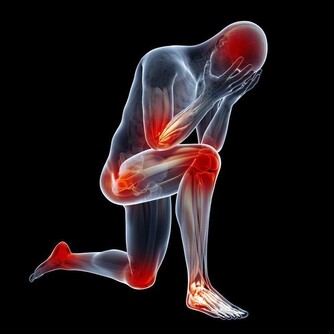

“抽筋”學名為肌肉痙攣,是指肌肉突然、不自主的強直收縮的現象。表現為肌肉突然變得很硬,疼痛難忍,可以持續幾秒到數十秒,多在游泳、睡覺或劇烈運動時出現。

常見的引起小腿抽筋的原因主要有寒冷刺激、肌肉代謝產物堆積、肌肉疲勞、局部肌肉短暫供血不足和缺鈣等。